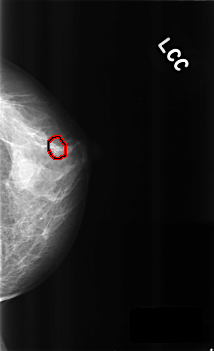

ics_version 1.0 filename C-0300-1 DATE_OF_STUDY 10 3 1995 PATIENT_AGE 38 FILM FILM_TYPE REGULAR DENSITY 3 DATE_DIGITIZED 5 8 1998 DIGITIZER LUMISYS LASER SEQUENCE LEFT_CC LINES 4560 PIXELS_PER_LINE 2776 BITS_PER_PIXEL 12 RESOLUTION 50 OVERLAY LEFT_MLO LINES 4528 PIXELS_PER_LINE 2792 BITS_PER_PIXEL 12 RESOLUTION 50 OVERLAY RIGHT_CC LINES 4632 PIXELS_PER_LINE 2928 BITS_PER_PIXEL 12 RESOLUTION 50 NON_OVERLAY RIGHT_MLO LINES 4648 PIXELS_PER_LINE 2896 BITS_PER_PIXEL 12 RESOLUTION 50 NON_OVERLAY |

FILE: C_0300_1.LEFT_CC.OVERLAY TOTAL_ABNORMALITIES 1 ABNORMALITY 1 LESION_TYPE CALCIFICATION TYPE PLEOMORPHIC DISTRIBUTION CLUSTERED ASSESSMENT 4 SUBTLETY 3 PATHOLOGY BENIGN TOTAL_OUTLINES 1 BOUNDARY |